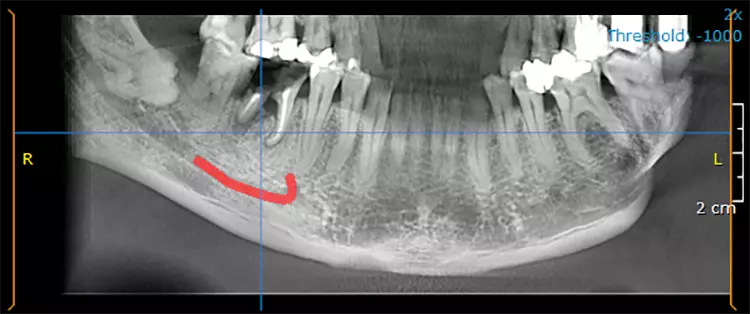

5. Multiple Sofortimplantationen in Zusammenhang mit internem Sinuslift

Beim vorliegenden 54-jährigen Patienten mussten aufgrund von lokaler Parodontitis die Zähne 25, 26 und 27 entfernt werden. Im apikalen Bereich lag jedoch gesunder Kieferknochen vor, sodass eine Sofortimplantation möglich war. Aufgrund der guten Einsichtbarkeit des Operationsgebietes nach Zahnextraktion konnte in diesem Fall flapless vorgegangen werden.

In regio 26 konnte das Implantat dabei komplett apikal im gesunden Knochen verankert werden. In regio 27 jedoch wurde lediglich eine Restknochenhöhe von 8 mm bestimmt. In diesem Fall wurde die Sofortimplantation mit einer internen Sinusbodenelevation nach Summerset kombiniert.